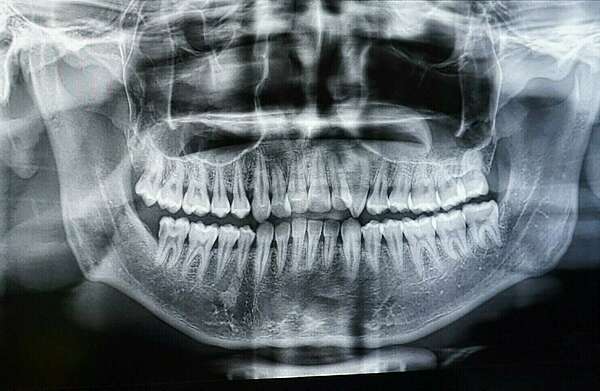

Un cliché est pris sur place lors de la 1ère consultation afin de voir l'ensemble de la denture et des articulations temporo-mandibulaires.